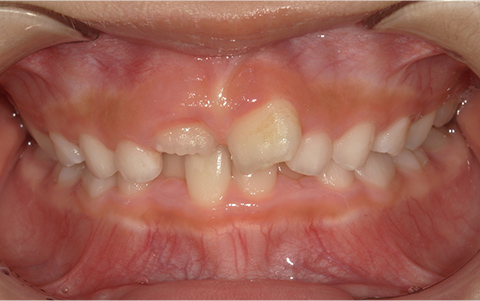

このような歯並びで

お悩みではないですか?

歯並びが悪い

前歯が出ている

症例